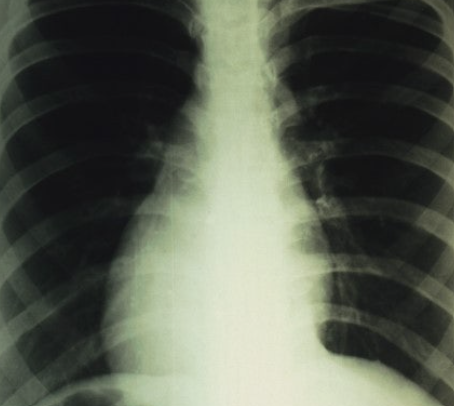

폐기흉은 폐에 구멍이 생겨 공기가 흉막강으로 유입되면서 폐가 정상적으로 기능하지 못하는 질환입니다. 초기에는 단순 통증으로 보일 수 있지만, 심각해지면 호흡부전으로 이어질 수 있어 조기 진단과 치료가 중요합니다.

폐기흉은 크게 자발성, 이차성, 외상성으로 구분됩니다. 특히 키가 크고 마른 체형의 젊은 남성, 흡연자에서 발생 위험이 높습니다. 자발성은 별다른 질환이 없는 상태에서 갑자기 나타나며, 이차성은 결핵이나 폐기종, 폐암 같은 기저 질환이 원인이 됩니다. 외상성은 교통사고, 수술, 시술 중 손상으로 발생합니다. 생활 습관과 기존 질환이 주요한 원인 요인으로 작용합니다.